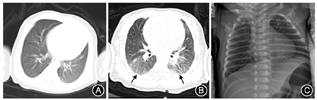

入院时5例患儿均出现局部胸膜线的病变,如欠光滑、增厚、模糊或消失,同时均出现不同程度的肺水肿征象,超声表现为密集程度、区域分布不一的B线,例5于双肺后上区、后下区胸膜下出现局灶性肺实变,实变肺组织内可探及充气支气管征象,与肺间质综合征改变毗邻、并存,见图1。患儿病程中、出院前复查肺部超声提示,与入院当日相比,肺水肿不同程度减轻,肺实变区消失,肺泡间质综合征程度明显减轻,见图2。

入院时肺部CT检查2例患儿未见实质性浸润,3例有肺部病变(1例为小条状模糊影,1例为胸膜下结节状稍高密度影,1例为双肺感染改变,可见不均匀磨玻璃样影)。病程中及出院前患儿复查胸部X线检查均提示影像学改变好转,程度较前减轻,见图3。超声检查5例患儿均可见胸膜线异常,均提示肺水肿(融合B线或肺间质综合征),1例患儿可探查到较表浅的肺实变征象。经临床治疗后所有患儿复查肺超声,各项声像图指标较前趋于好转。患儿入院时肺部超声与肺部CT结果见表1。

COVID-19患者病变部位大部分位于双肺外带胸膜下,病灶多发,但成人分布更广泛、弥散[6],成人COVID-19主要肺部病变的超声声像图特征为肺间质综合征、肺实变和胸腔积液[7]。当炎症引起肺内气体减少、肺泡内含液量增多,间质及周围血管水肿,超声图像上表现范围不等的B线,能反映肺脏含水量增加[8],随着病情的进展,渗出液增多,肺泡塌陷,纤维组织增生,形态学上出现不同程度肺实变。本组5例患儿肺部超声均提示有不同程度肺水肿改变,其中3例肺部超声表现为散在B线,部分肺区发现融合B线,提示患儿存在轻度肺水肿;1例患儿部分肺区可见密集的B线呈火箭征,考虑为肺间质综合征,提示该患儿存在中度的肺水肿,这也印证了关于肺水肿是COVID-19主要的病理表现这一说法[9];1例患儿双肺后区可见胸膜下小片状实变,周围组织呈肺间质综合征,其声像图表现与新生儿呼吸窘迫综合征类似,但病变范围较局限,仅累及双肺后区。住院第6天复查超声双肺未见实变区,病灶较前减小,双肺后下区可见多发密集分布的B线,呈肺泡间质综合征表现。本组5例患儿均出现不同范围的胸膜线增厚、模糊,考虑与病灶主要位于胸膜下或肺野外带,炎性渗出累及胸膜导致局部的胸膜反应[10],异常肺部超声征象在肺下叶为主,与余成成等[11]报道基本一致,这可能与病理性肺炎早期累及终末细支气管和呼吸性细支气管等病理机制有关。病程中患儿肺部B线逐渐减少,胸膜线和A线恢复,实变区消失,证实临床操作中肺部超声对病情评估的可行性。